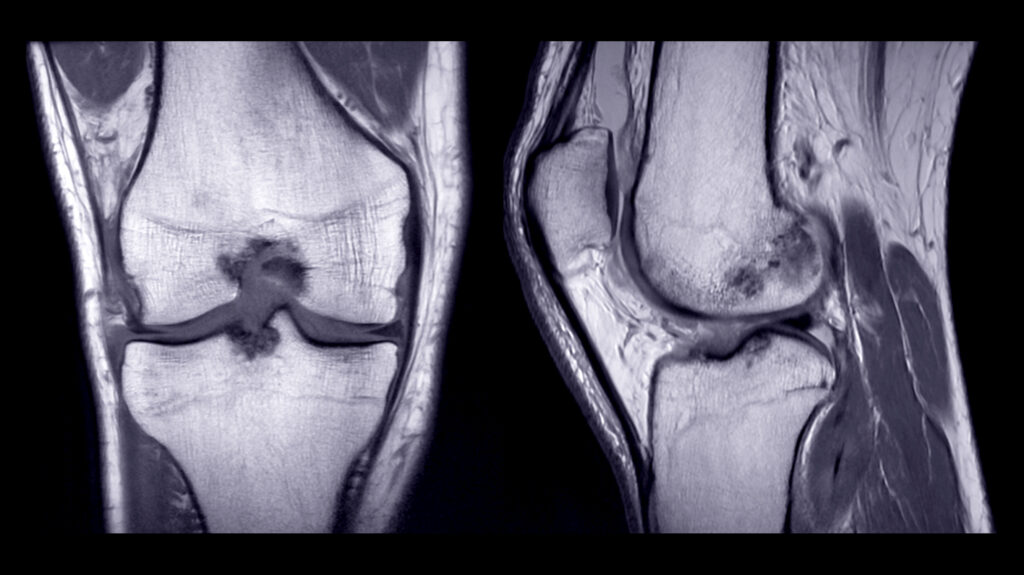

How a Knee MRI Helps Diagnose Sports and Injury Pain

Knee MRI Florida: Discover How Imaging Reveals the True Cause of Sports Injuries Knee injuries can sideline athletes and active people from the activities they love. One wrong pivot during basketball, a fall while running, or a collision during soccer can cause serious damage. When knee pain persists after an injury, you need answers about […]